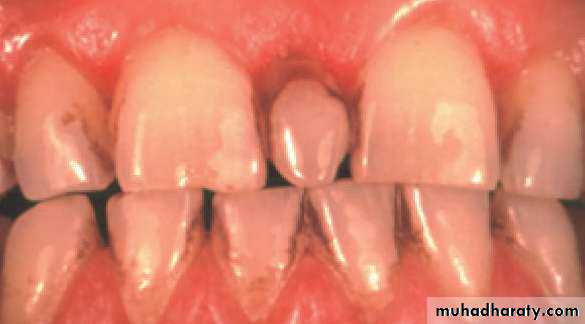

• Mesiodens :When they occur between the maxillary central incisors.

• Common region of the jaws to be affected is the premaxilla.

Many supernumerary teeth never erupt, but they may delay eruption of nearby teeth or cause other dental problems.

If they erupt, they can cause malalignment of the normal dentition.